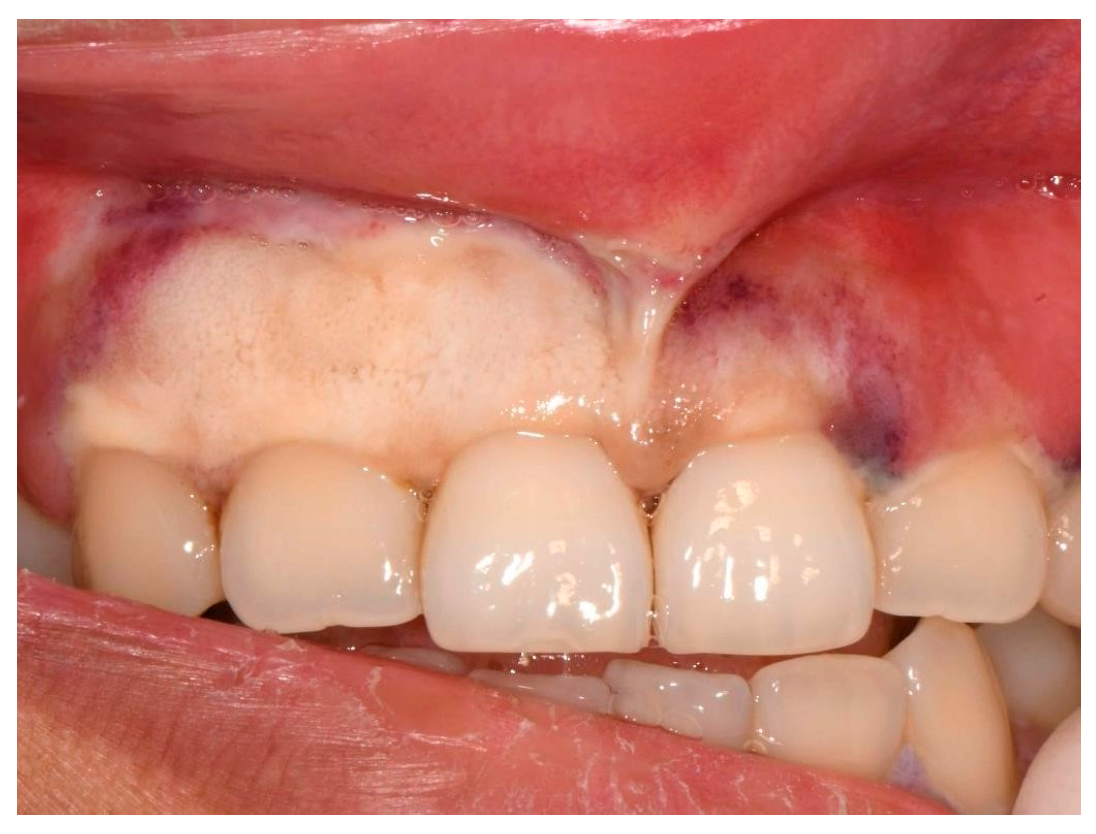

2. Case Presentation